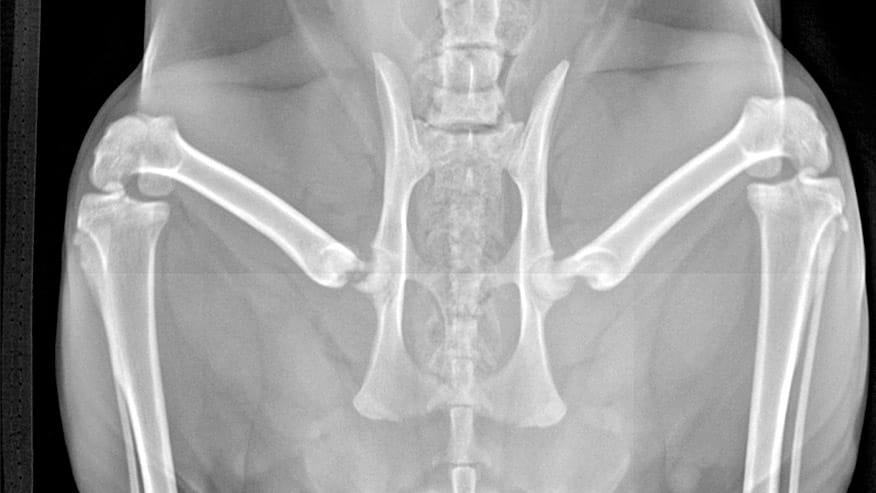

• VCA Cat Hospital of Philadelphia Digital Radiology

Our hospital is proud to offer state-of-the-art Digital Radiology Services. Digital x-rays are essentially film-less x-rays. Traditional x-rays use photographic film to capture images whereas digital x-rays use a digital image capture device (computer) to record the x-ray image.... Read more